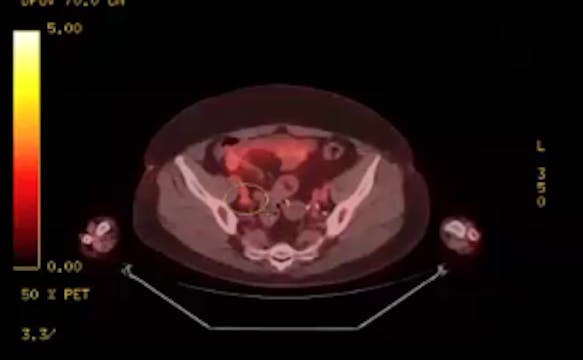

02/08/2023 - Dr. Christine Fisher - Radiation Oncology - US GYN

endometrial adenocarcinoma, para-aortic nodes, PET CT, diabetes, charcot arthropathy, groin nodes, pelvis, negative cervical margins, cisplatin, small bowel, Harkenrider, contouring, MRI, tumor, vaginal bleeding, relapse, persistence, cylinder, dose distribution, dosimetry, brachytherapy, fractionation, concurrent chemotherapy, parametrial area